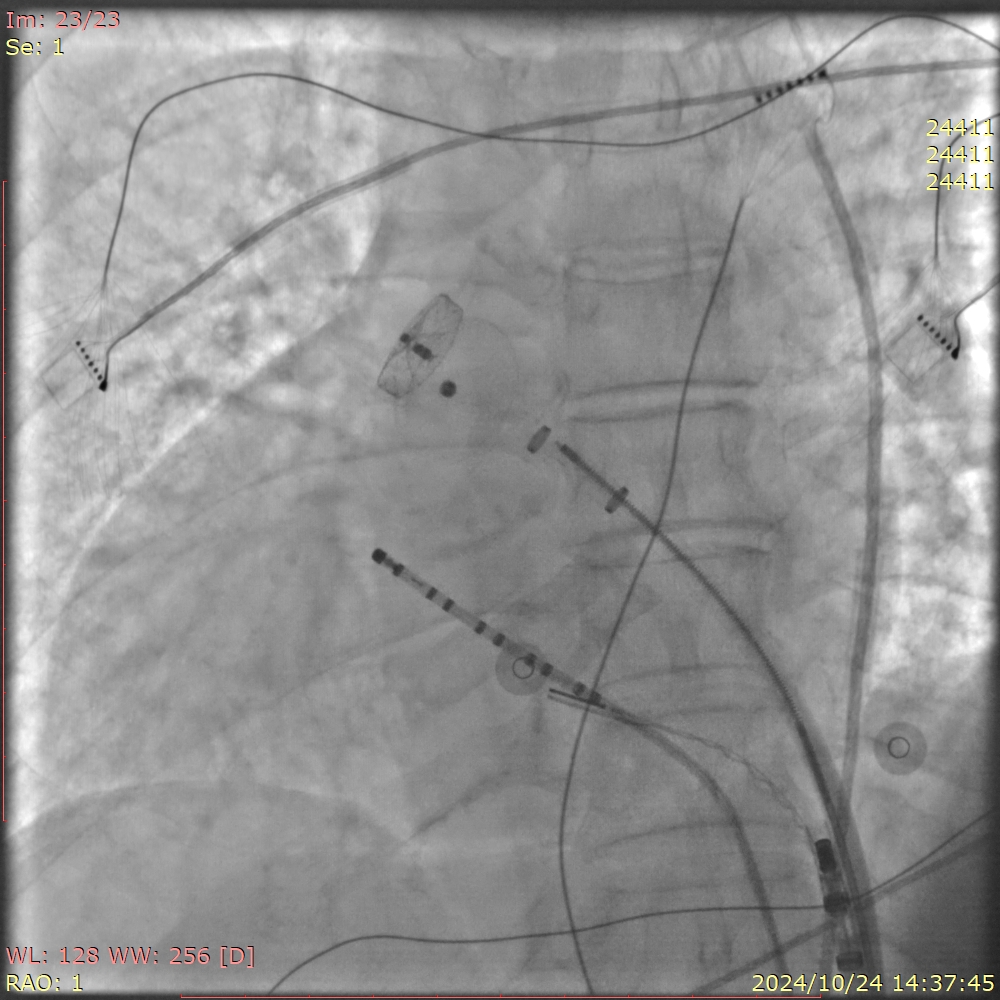

手术过程中,王洪涛教授亲自操刀,充分利用CARTO 3三维标测系统,实现了精准定位和消融,成功为患者实施了房颤射频消融术。随后,团队又克服了镜面右位心带来的操作困难,使用新一代国产左心耳封堵器LACbes成功完成了左心耳封堵术,有效预防了卒中的发生。王洪涛教授解释:“房颤射频消融术能够消除房颤的症状,而左心耳封堵术则能够闭合房颤患者血栓发生的根源部位,两者结合能够大大降低患者的卒中和出血风险。”